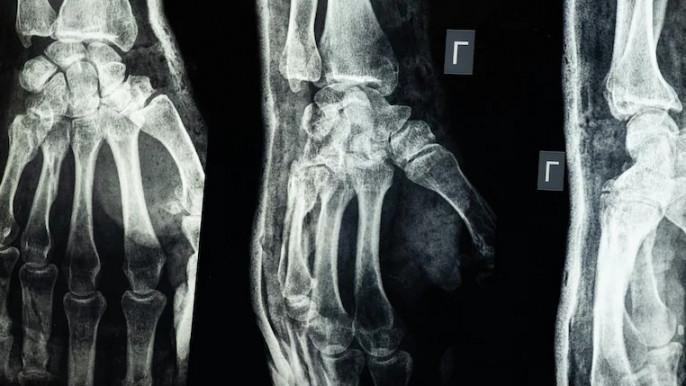

“ერთ-ერთ კლინიკურ შემთხვევაში, პაციენტს, რომელსაც მაჯის მოტეხილობა ჰქონდა, ერთი ინიექცია გაუკეთეს და სულ რაღაც 3 წუთში განიკურნა,“ - იტყობინება ადგილობრივი მედია.

გამოცემის ცნობით, ტრადიციულად, მაჯის აღსადგენად საჭირო იქნებოდა ოპერაცია, ლითონის ფირფიტისა და ხრახნების ჩასმა, რომელთა ამოსაღებად მეორე წელს ხელახალი ოპერაციის გაკეთება მოუწევდა პაციენტს. ანგარიშში ნათქვამია, რომ ძვლის წებოს გამოყენებიდან სამი თვის შემდეგ დადგინდა, რომ პაციენტის მაჯის მოტეხილობა სრულიად შეუხორცდა, ყოველგვარი გართულებების გარეშე.